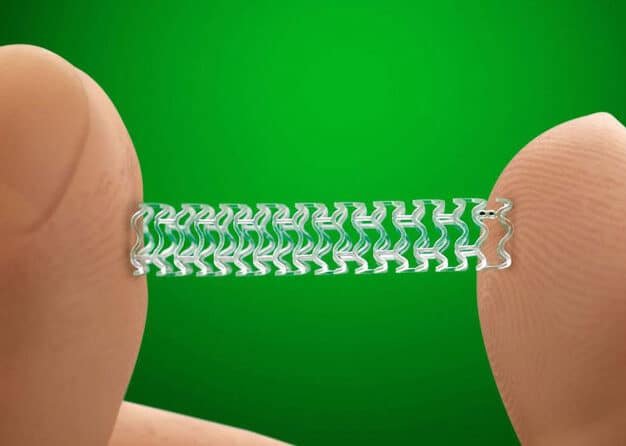

Los stents biodegradables que desaparecen tras curar la arteria representan un avance revolucionario en el tratamiento de...